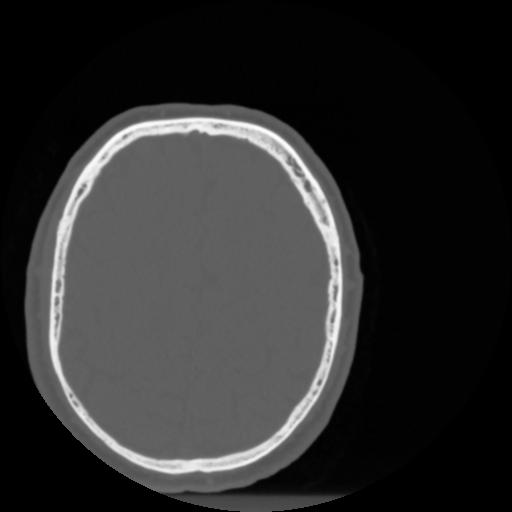

4 CEREBRO,,Vol,0.5,CEREBRO,,